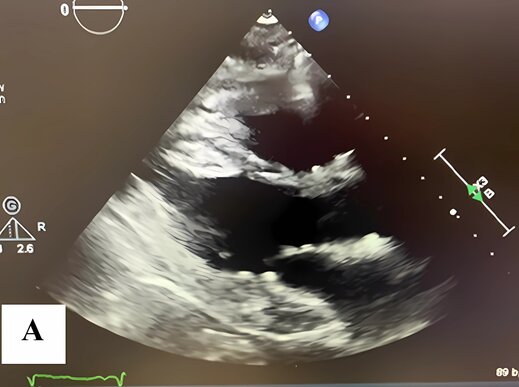

A follow-up transthoracic echocardiogram, performed approximately two months after discharge, revealed complete normalization of left ventricular systolic function, with an estimated ejection fraction of 70–75%. There were no regional wall motion abnormalities, and only mild grade I diastolic dysfunction persisted (average E/e′ = 11). Trivial pericardial effusion and a small residual left pleural effusion were present. Additionally, mild mitral valve leaflet calcification was observed without stenosis or regurgitation (Figure 6(a) and (b)). These findings confirmed full recovery from Takotsubo cardiomyopathy and complete resolution of the apical thrombus. The patient remained clinically stable with no recurrence of symptoms during follow-up.

Figure 6. A follow-up transthoracic echocardiogram was performed approximately two months after discharge.

(A) Systolic and (B) Diastolic images show complete normalization of left ventricular function, with resolution of apical ballooning and absence of thrombus.